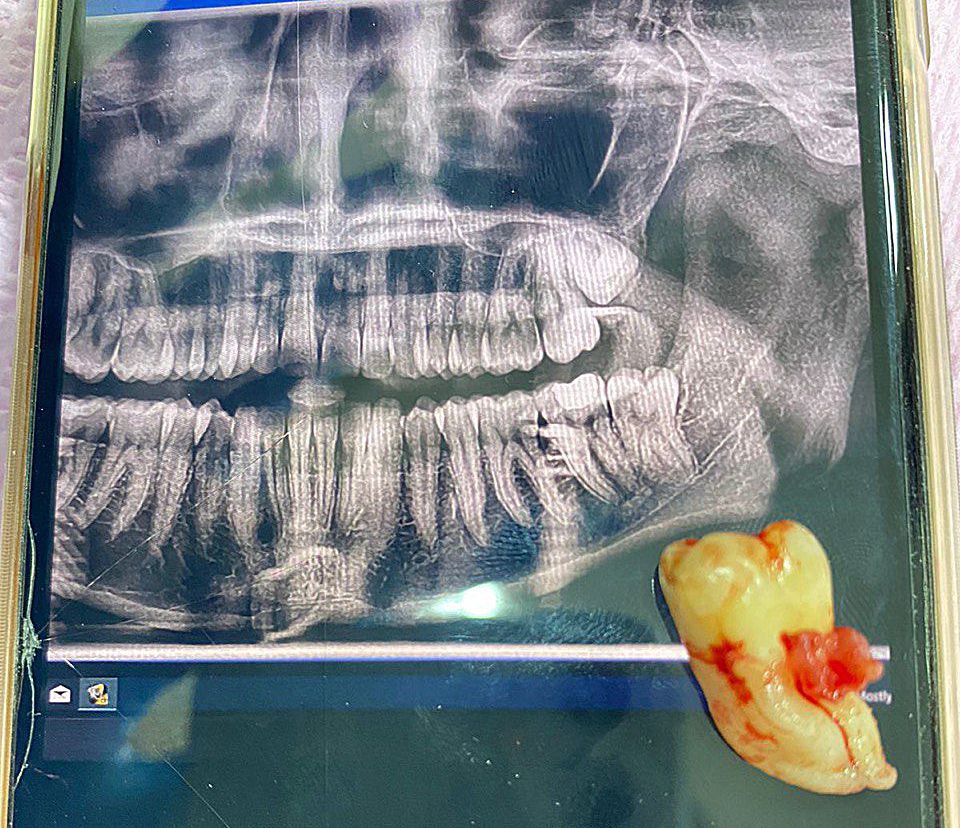

Surgical extraction of wisdom tooth in the dental surgery clinic